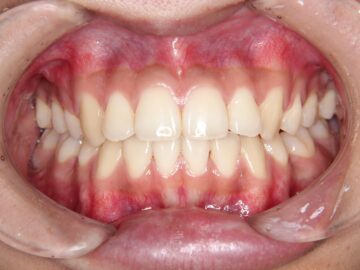

開咬(顎位不安定・自費治療・クリアタイプブラケット)

16歳 男性

ご相談時

治療後